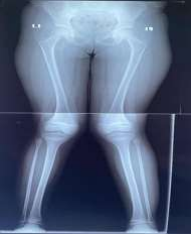

Figure 5